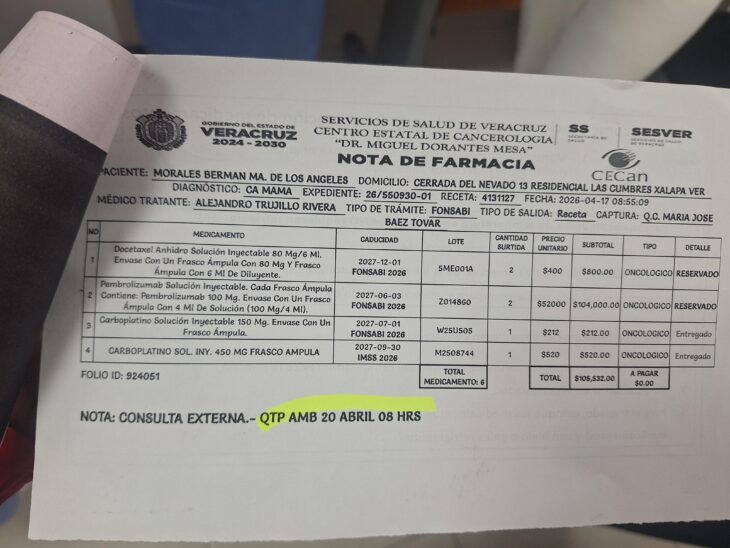

Denuncian desabasto de insumos para quimioterapia en el CECAN

Pacientes que reciben tratamiento oncológico en el Centro Estatal de Cancerología Dr. Miguel Dorantes Mesa (CECAN) manifestaron su inconformidad ante el desabasto de insumos indispensables para la aplicación de quimioterapias, […]